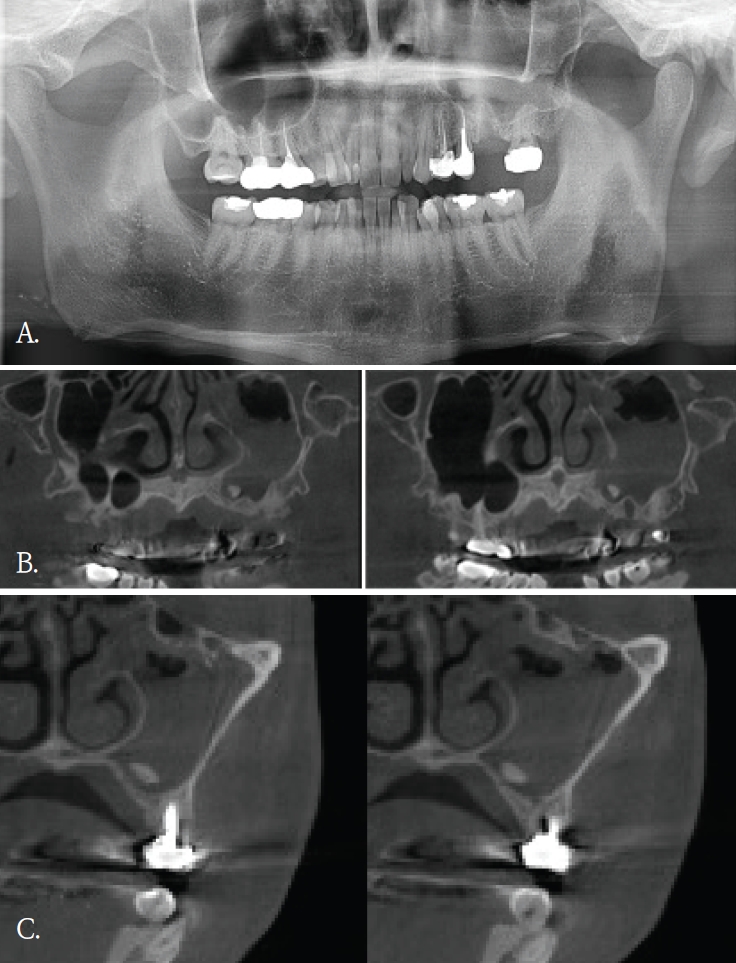

50대 여자환자가 상악 전치부 임플란트치료를 위해서 콘빔 CT검사를 시행하였다. 파노라마방사선영상에서는 해당 부위에 특이 소견이 뚜렷하지 않았다(Fig. 2A). 그러나 콘빔CT의 축상면 및 횡단면 영상에서 양측 상악동 전벽에 인접한 안면 피하 연조직을 따라, 반달모양의 경계가 명확하고 내부가 균질한 음영을 보이는 구조물이 관찰되었다(Figs. 2B and C). 해당 소견은 주된 촬영 목적과 무관하였고 양측에서 대칭적으로 관찰되었으며 관련 증상이 동반되지 않았다. 임상 소견 및 영상 소견을 종합할 때 병변 가능성은 낮다고 판단하였고, 위치와 형태를 고려하여 피하에 주입된 미용필러에 의한 소견으로 판단하였다. 이에 추가 처치는 시행하지 않았다.

A. Panoramic radiograph shows no definite abnormality in the maxilla. B. Axial cone-beam computed tomographic (CBCT) image shows crescent-shaped radiopaque foreign bodies along the anterior walls of the bilateral maxillary sinuses (arrows). C. Cross-sectional CBCT image also demonstrates the same findings on a different plane (arrows).

한편, 안면미용시술을 받은 환자들이 치과에 많이 내원하면서 우연히 발견되는 이물질 소견 중 하나가 미용 필러이다[9]. 치과의사들에게 아직은 익숙하지 않은 방사선영상 소견이고 부위도 치아나 악골이 아닌 연조직부위에서 관찰되기에 영상 판독에서 배제될 가능성이 있다. 미용필러도 파노라마방사선 영상에서보다는 콘빔CT영상에서 위치나 형태, 양상을 잘 관찰할 수 있다.